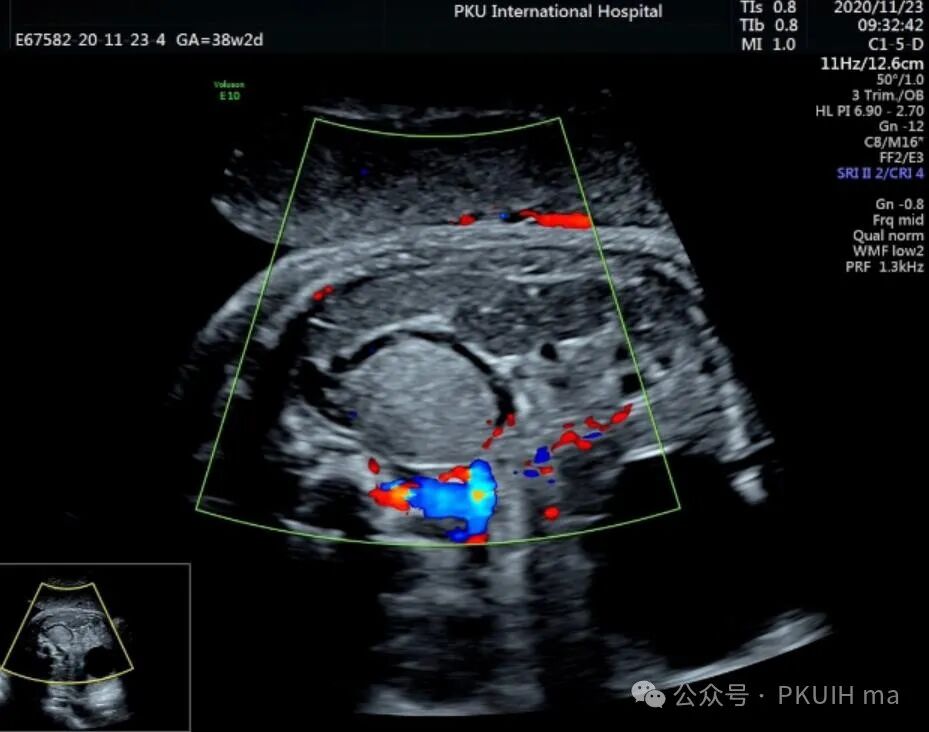

上图是一例在孕晚期发现的肾上腺占位,生后病理证实为神经母细胞瘤的患儿,生后及时做了治疗预后非常好,目前宝宝各项指标都很好。

同时在孕晚期也发现孕妇羊水增多

这几年我们在孕晚期发现有3例神经母细胞瘤胎儿,预后都很好。在孕晚期超声中建议常规扫查下胎儿双肾区